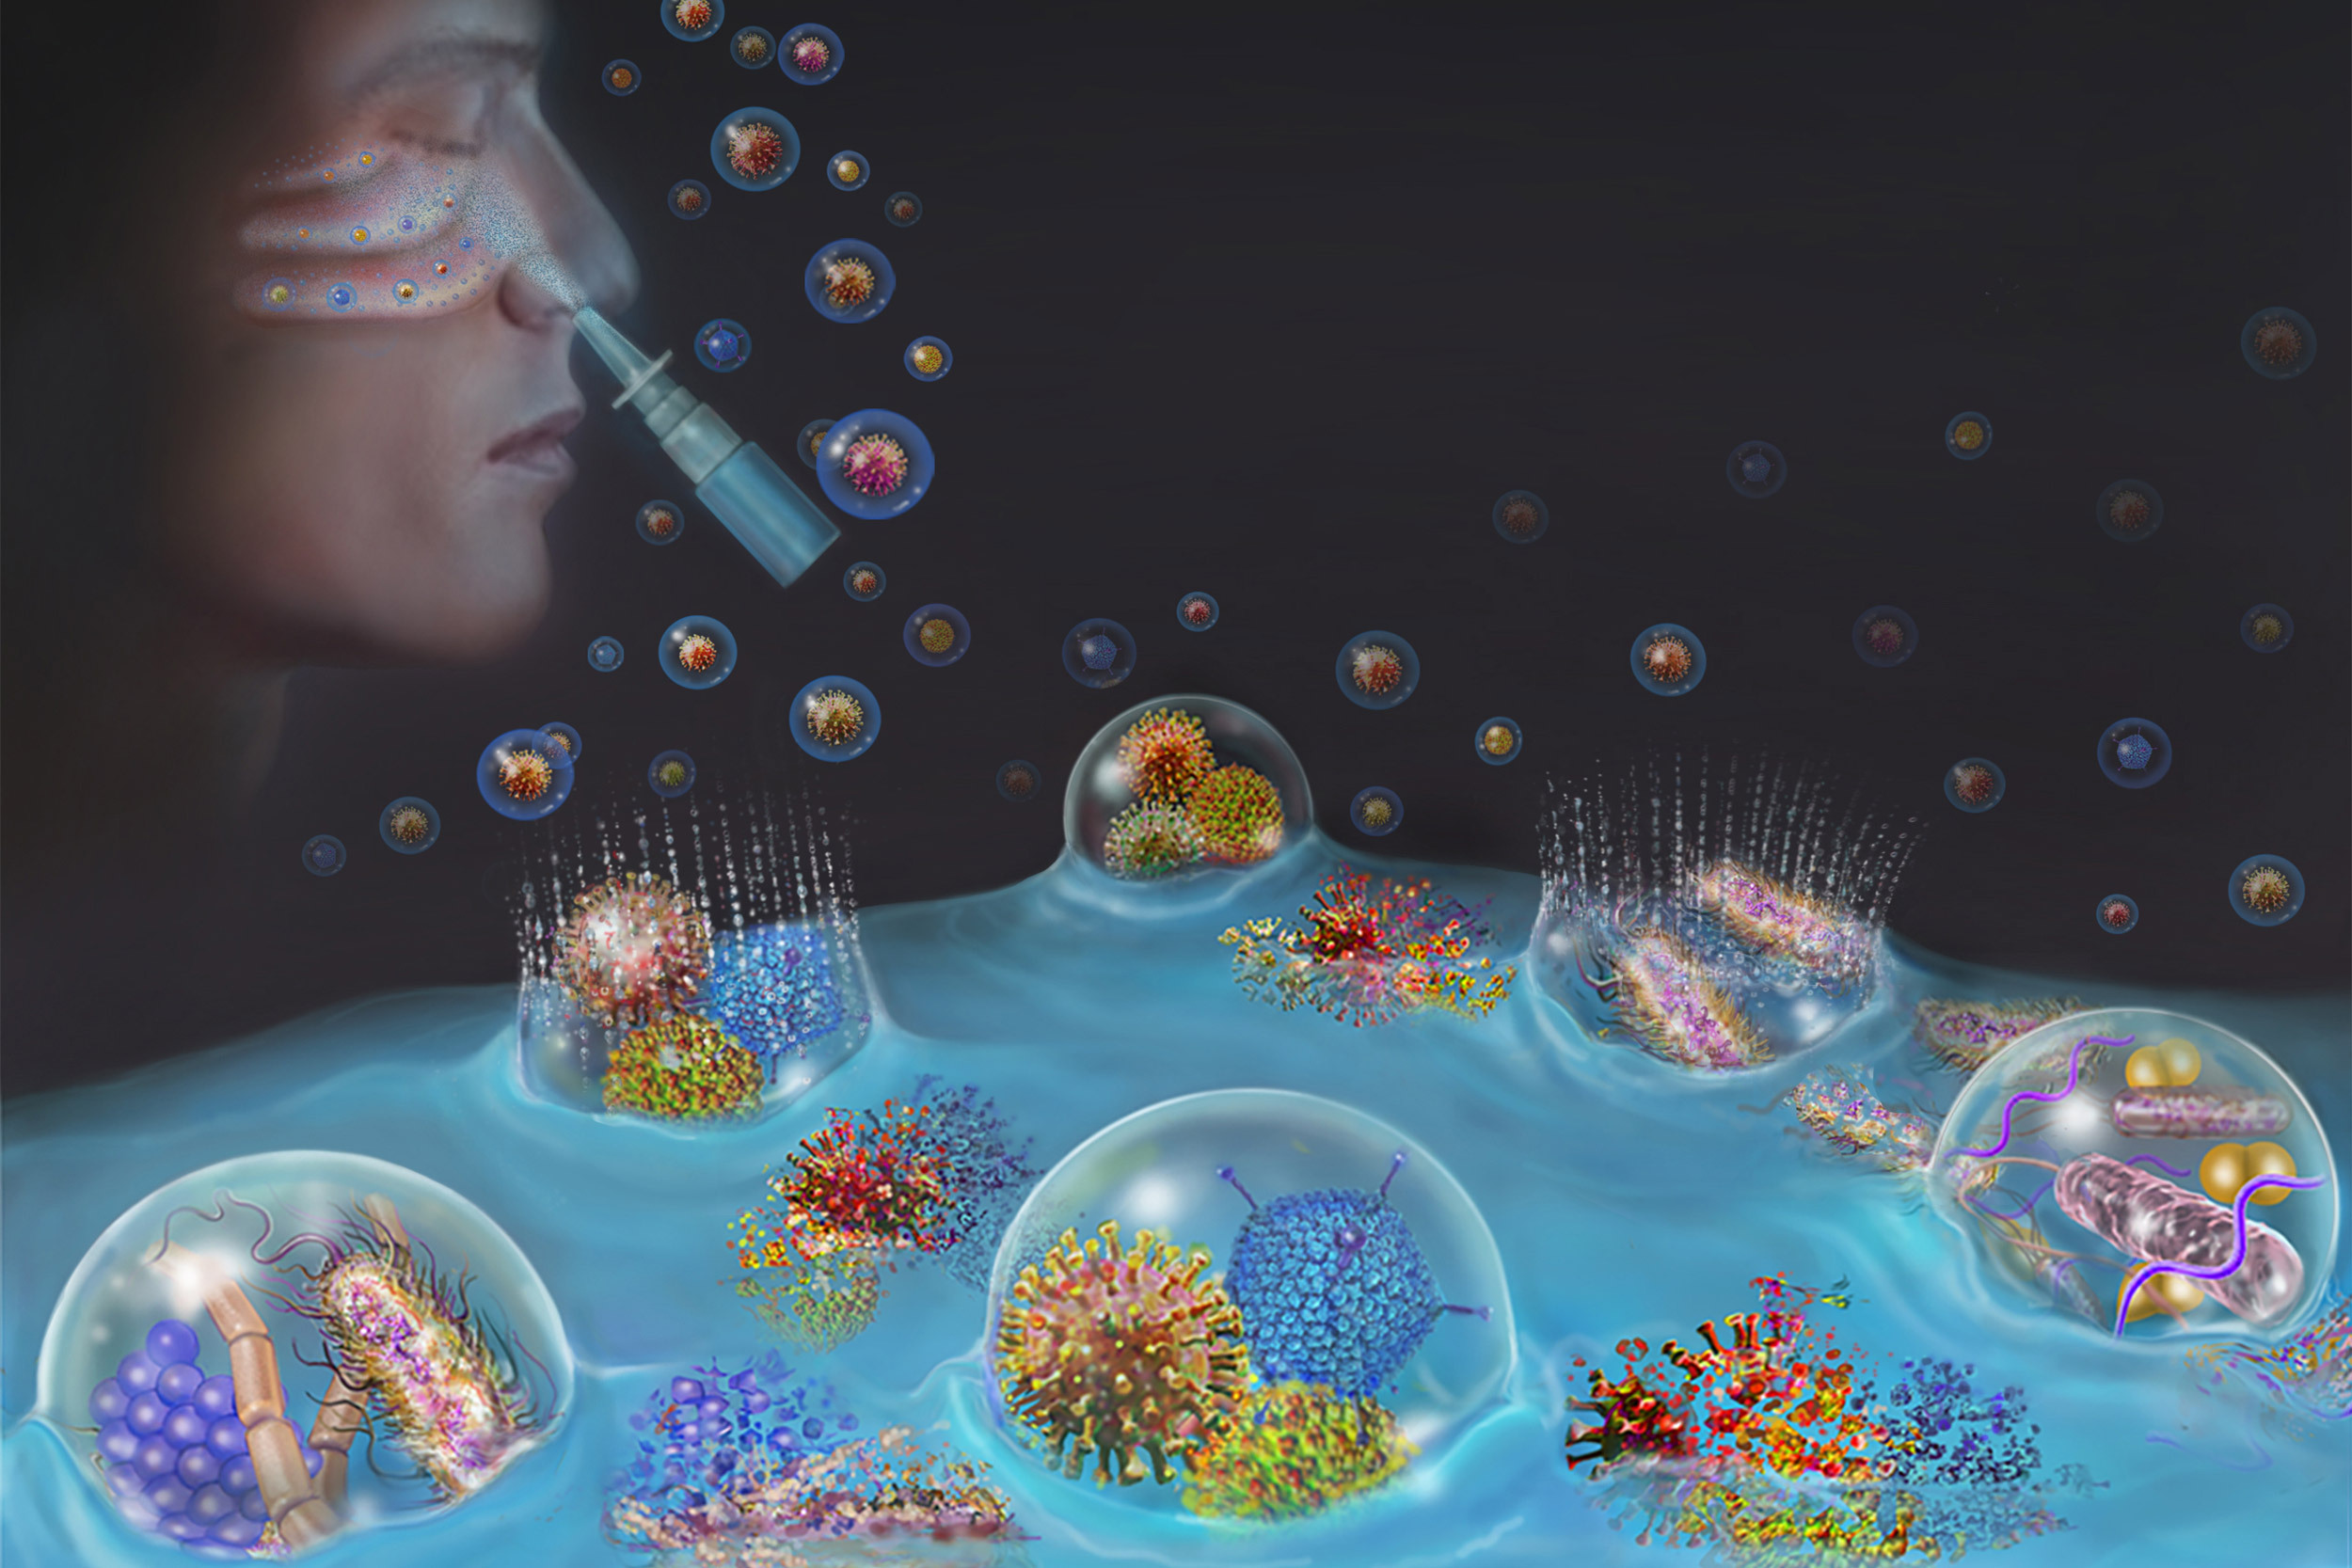

Sorry by experimental what I meant here is something which is not ready to be tested in humans - this scientist was skipping a bunch of the necessary steps to show this is a safe thing to do (in lab grown cells first, for example) to proceed to human experimentation.

Yes, but if a review board were to sign off on them and then someone managed to significantly hurt or damage themselves, one could theoretically apply some of the blame to the review board for not doing their job to ensure that a study was safe. The whole idea of having ethics as a part of the review board was born of some of the studies they used to sign off on that were ultimately problematic and resulted in seriously damaging some individuals, such as minorities and kids.